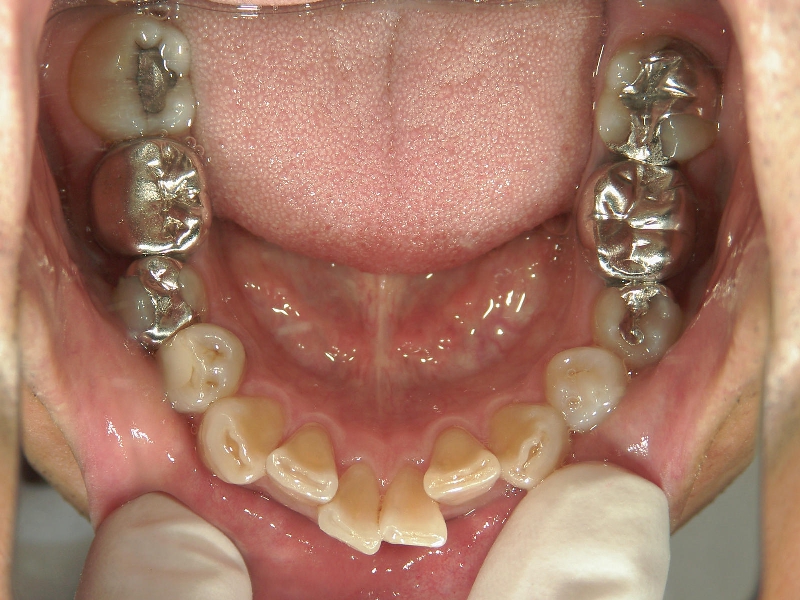

主訴:下の歯がガタガタ。

矯正歯科 治療前 右上4番、左右下4番 計3本抜歯し、叢生を改善

矯正_灰色.pngno.22_8175_治療前_下.jpg矯正_灰色.png